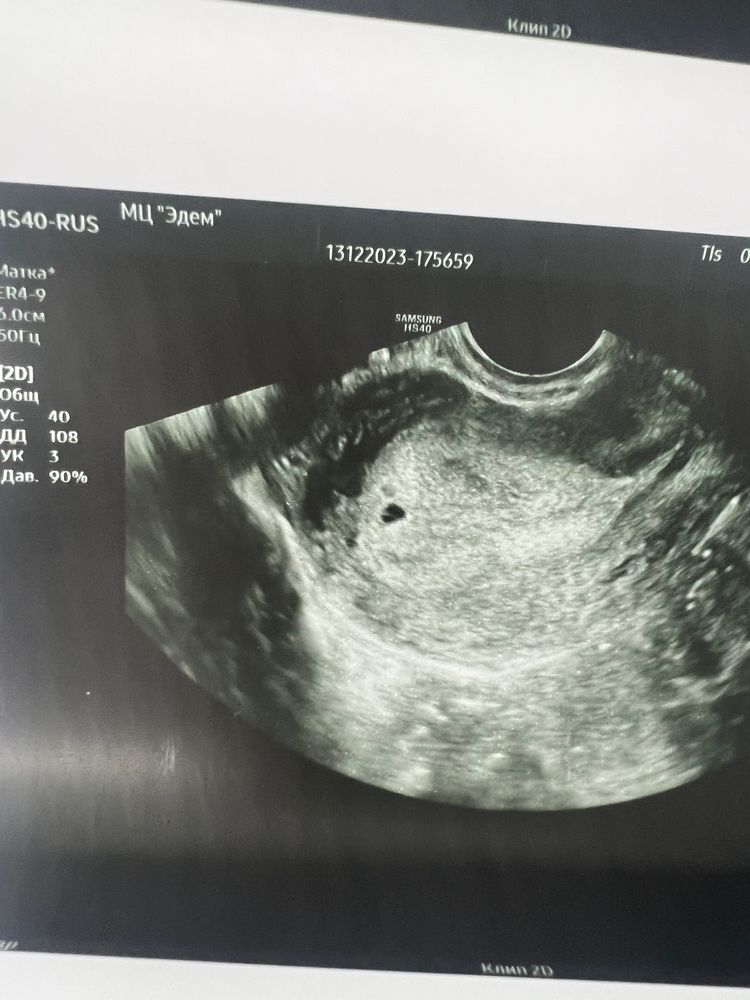

5 дней от первого положительного теста до узи тянулись вечно🙈 я боялась, что ХГЧ не успеет дорасти до визита ко врачу, но все получилось) Яйцо в дне полости матки (пока маленькое совсем, врач сказала, что только-только стало видимым), сказали положение хорошее. Желтое тело 23мм в левом яичнике (как раз его и чувствовала в овуляцию). Хгч сдавала сегодня утром (первые два были в середине дня, сегодня на 7 часов раньше предыдущих ) - сегодня было 1059, позавчера 517, еще два дня назад 211. 27 декабря второе узи, очень хочу увидеть эмбрион и услышать сердцебиение🥰🤞